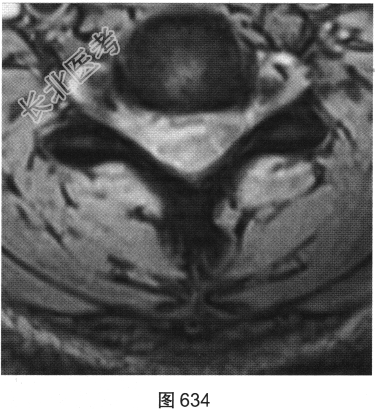

- [材料题] 患者女性,49岁,颈部胀痛伴双手麻木3天。MRI检查见图632~图637。

- 多项选择题1.患者MRI图片有哪些阳性征象( )

A、同水平硬膜囊及脊髓明显受压

B、病变与硬膜夹角为钝角

C、病变呈环形强化,中心未见明显强化

D、病变在髓外硬膜下

E、病变跨越右侧椎间孔,呈哑铃状改变

F、C

水平硬膜外梭形软组织信号

- 多项选择题2.根据MRI表现,患者可能的诊断是( )

A、脊柱淋巴瘤

B、椎间盘脱出、髓核游离

C、神经纤维瘤

D、后纵韧带骨化

E、神经鞘瘤

F、硬膜外血肿